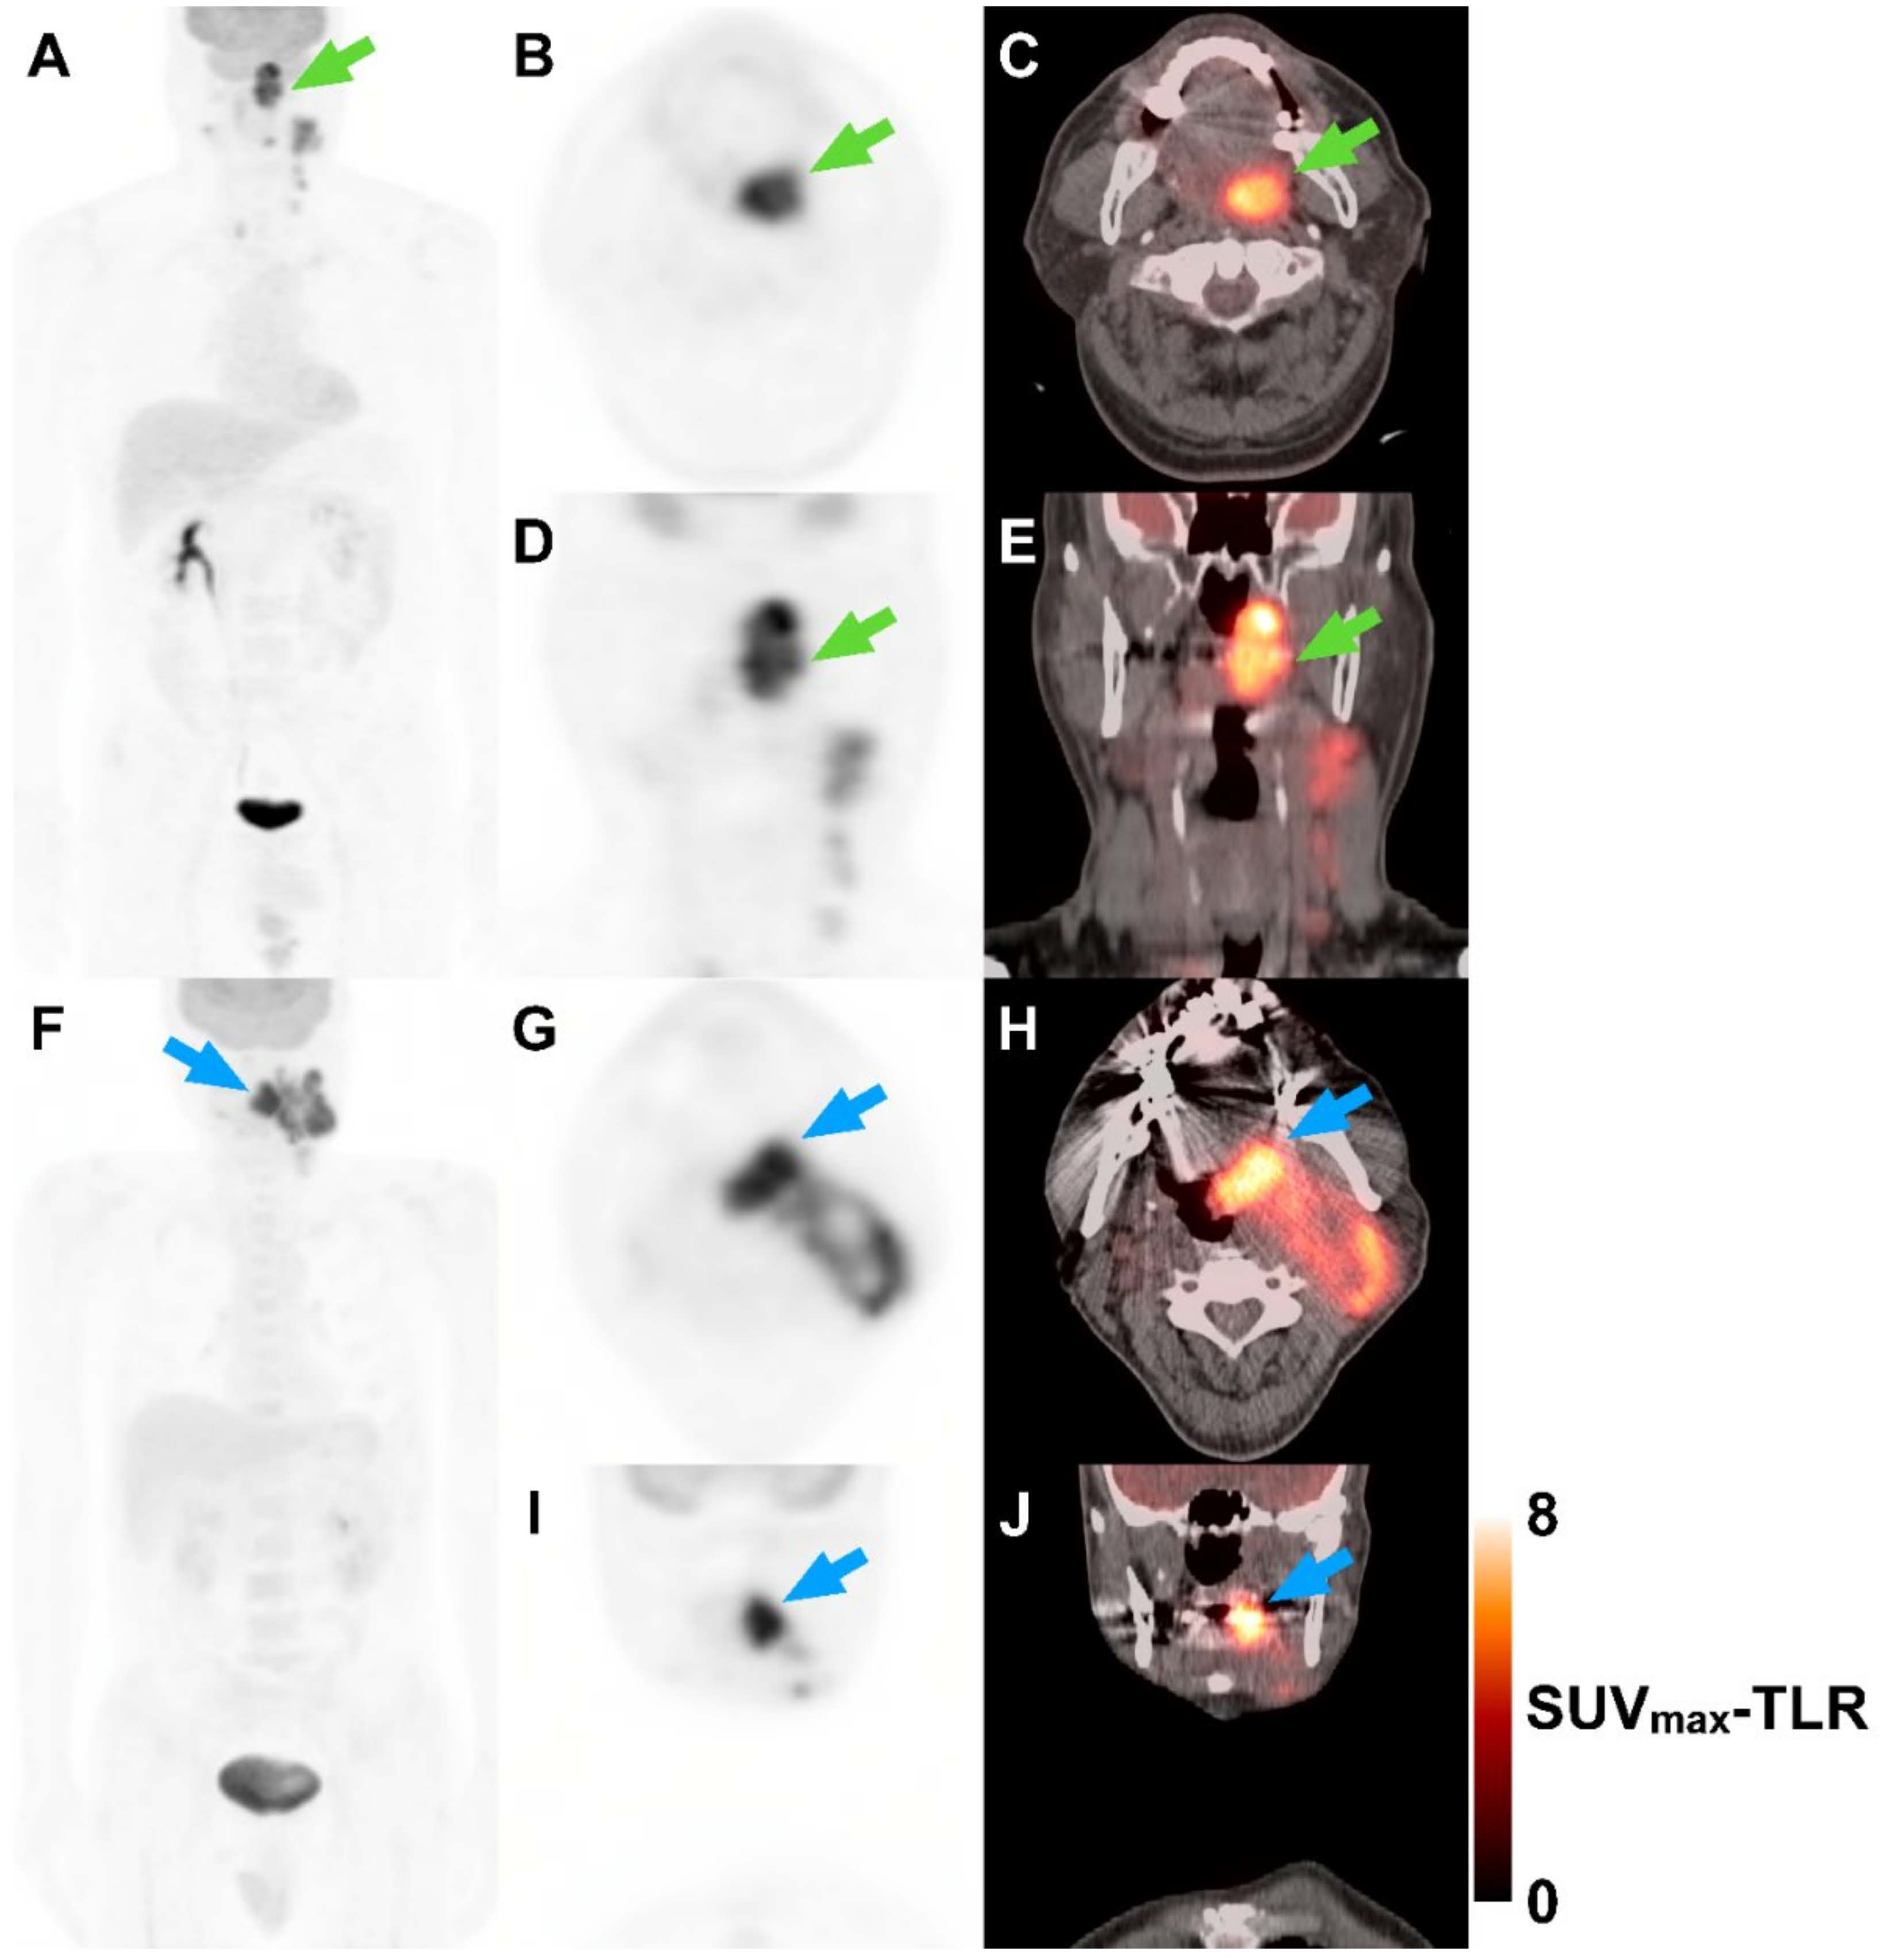

Figure 3.

Two representative cases show that patients’ outcomes could be estimated based on metabolic parameters. A 59-year-old man with HPV-related oropharyngeal cancer squamous cell carcinoma (OPSCC) (A–E). Maximum intensity projection (A), axial and coronal PET (B,D), and fused PET/CT (C,E) images demonstrate left tonsillar mass with bilateral cervical lymph node metastasis. The primary tumor shows heterogeneous FDG uptake (green arrows). The TNM designation is T4N2M0 with a prognostic grouping of stage III. Tumor SUVmax to liver SUVmean ratio (SUVmax-TLR) and coefficient of variation (CV) are 8.0 and 34.5%, respectively. The patient progressed after 11.6 months and died after 28.8 months. Another 59-year-old man with HPV-related OPSCC (F–J). Maximum intensity projection (F), axial and coronal PET (G,I), and fused PET/CT (H,J) images reveal left tonsillar mass with bilateral cervical lymph node metastasis. The primary tumor shows relatively homogeneous FDG uptake (blue arrows). The TNM designation is T4N3M0 with a prognostic grouping of stage III. SUVmax-TLR and CV are 7.0 and 27.9%, respectively. The patient has not progressed or died during the 63.8-month follow-up.